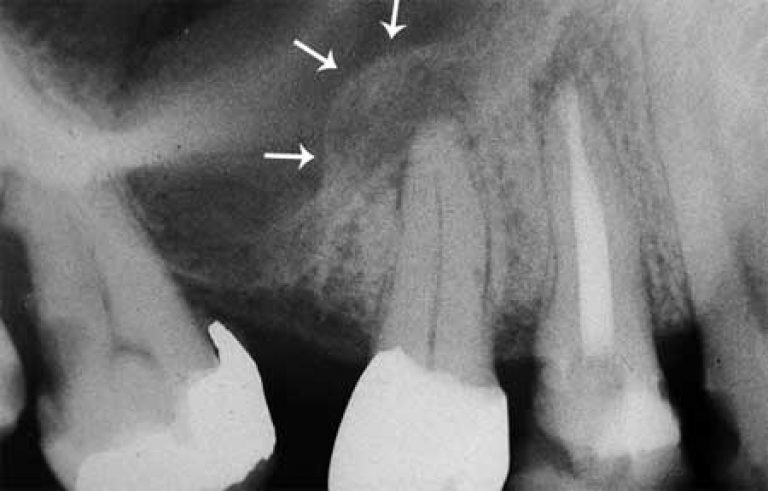

Периапикальный абсцесс мкб

Периапикальный абсцесс мкб 105 фото